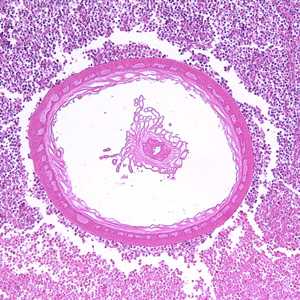

Acanthocephalans in tissue, stained with hematoxylin and eosin (H & E).

Figure A: Transverse section through the body wall of Bolbosoma sp. in an intestinal biopsy specimen, stained with H&E. Image taken at 100x magnification. Cetaceans are the normal definitive hosts for Bolbosoma spp., and humans usually become infected after eating under-cooked fish which serve as paratenic hosts for the parasite.

Figure B: Higher-magnification (200x) of the specimen in Figure A. Identifiable in this image are the characteristic thin cuticle (CU, black arrow), syncytial epidermis (EP), longitudinal muscles (blue arrows) and eggs (green arrows).

Figure C: Transverse section through the body wall of Bolbosoma sp. in an intestinal biopsy specimen, stained with H&E. Image taken at 100x magnification. In this image, a portion of the reproductive system is visible within the pseudocoelom.

Figure D: Cross-section of the intestine of a pig, stained with H&E, showing the anterior end of an adult Macracanthorhynchus hirudinaceous embedded within the intestinal wall.